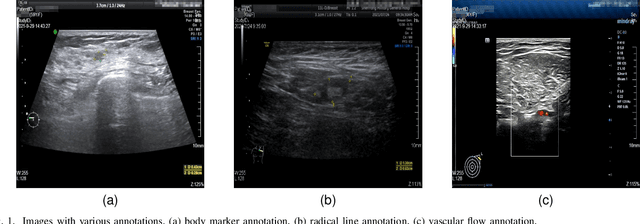

Abstract:Accurately annotated ultrasonic images are vital components of a high-quality medical report. Hospitals often have strict guidelines on the types of annotations that should appear on imaging results. However, manually inspecting these images can be a cumbersome task. While a neural network could potentially automate the process, training such a model typically requires a dataset of paired input and target images, which in turn involves significant human labour. This study introduces an automated approach for detecting annotations in images. This is achieved by treating the annotations as noise, creating a self-supervised pretext task and using a model trained under the Noise2Noise scheme to restore the image to a clean state. We tested a variety of model structures on the denoising task against different types of annotation, including body marker annotation, radial line annotation, etc. Our results demonstrate that most models trained under the Noise2Noise scheme outperformed their counterparts trained with noisy-clean data pairs. The costumed U-Net yielded the most optimal outcome on the body marker annotation dataset, with high scores on segmentation precision and reconstruction similarity. We released our code at https://github.com/GrandArth/UltrasonicImage-N2N-Approach.